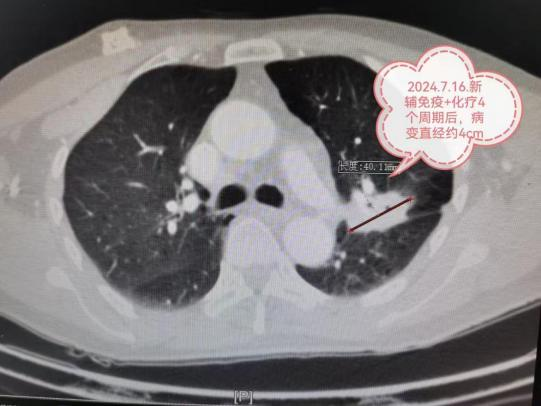

近日,贵州航天医院接诊了一位59岁的男患者,吞咽时总有哽噎感,心里特别担心是癌症,在做完增强CT、超声胃镜等检查后,确诊为食管平滑肌瘤,直径约3.5厘米,是良性肿瘤。不过,这颗瘤子的位置有点棘手——长在气管分叉处的食管壁里,周围挨着大血管、神经和气管,传统开胸手术创伤大,恢复慢;单用胸腔镜,万一伤到食管粘膜不好判断;单用胃镜,瘤子太大又容易切不干净或穿孔。 怎么办?心胸外科、消化内科、麻醉科等科室一起坐下来会诊(MDT),最终定下了一个“内外配合”的方案:双镜联合——胸腔镜+胃镜食管平滑肌瘤摘除术。 手术当天,心胸外科团队从右胸一个约3厘米的小孔进入,完整剥出肿瘤,并避免了周围血管、神经、气管的损伤,紧接着,消化内科团队用胃镜检查,确认摘除肿瘤后的食管粘膜完好,1个多小时便为患者顺利完成手术;术后第2天,患者就能顺利进食,哽噎感消失,第4天,康复出院。 “双镜联合”食管平滑肌瘤摘除术的优势 ※创伤小:不用开胸,不用切断肌肉、撑开肋骨,胸部仅留一个3厘米小口。 ※看得准:内外镜配合,完整摘除肿瘤的同时,当场就能检查食管粘膜有无破损。 ※并发症少:出血少,安全性高,患者少遭罪。 科普小知识 食管平滑肌瘤是什么? 简单说,它就是长在食管壁粘膜下的一颗良性“肉疙瘩”,食管表面粘膜是光滑完整的,不像食管癌那样会破溃,很多人没症状,体检时偶然发现,有症状的话,常见就是胸骨后不舒服、吞咽时有哽噎感,但大多比较轻,时好时坏,生长很慢,少数会长得很大,引起明显吞咽困难。 怎么治? 瘤子小、没症状:定期复查,不用急着手术。 瘤子持续长大、有压迫症状:需要手术摘除。 所以,吃东西有哽噎感,先别自己吓自己,去医院做个检查,就算是肿瘤,也可能是良性的。即便需要手术,现在也有这种“内外夹击”的微创办法,恢复快,还不遭大罪。 贵州航天医院心胸外科专家简介 陈光春 心胸外科主任、学科带头人,医学硕士,副主任医师 从事胸外科临床工作近30年,原部队军医,曾工作于陆军军医大学附属大坪医院胸外科(全军唯一胸外科研究所)。 临床擅长:对肺结节、肺肿块、肺癌、血气胸、脓胸、食管癌、食管裂孔疝、反流性食管炎、纵隔肿瘤、胸腺瘤、重症肌无力、手汗症、胸部外伤等疾病的诊疗有丰富的临床经验。擅长胸腔镜肺癌、食管癌、纵膈肿瘤切除术等大型胸外科微创手术,特别擅长单孔胸腔镜微创手术;熟练掌握3D-技术引导下亚肺叶切除术、不插管保留自主呼吸胸外科手术(Tubeless手术)等最先进的胸外科微创技术,设计并开展西南地区首例经左胸单孔辅助腹腔镜胃食管交界部肿瘤微创手术。 中国防痨协会胸外科分会常务委员,中国医师协会手汗症专委会委员,吴阶平医学基金会交感神经外科专委会委员,重庆市医药生物技术协会肺癌、食管癌防治专委会委员,贵州省研究型医院学会胸外科专委会常务委员,2024年参与制定了《手汗症ETS微创技术优化与日间手术质量控制中国专家共识》。曾荣获重庆医科大学“受学生好评教师”称号和教学比赛第一名。发表学术论文10余篇。 罗明洋 中共党员,心胸外科副主任,副主任医师 临床擅长:从事胸外科工作近20年,对胸部外伤、胸壁重建、气胸、脓胸、包裹性胸腔积液、肺结节、肺肿块、肺癌、食管癌、纵隔肿瘤等胸外科疾病的诊治具有丰富的临床经验,特别擅长肺癌、食管癌、纵隔肿瘤的电视胸腔镜微创手术。 贵州航天医院心胸外科简介 心胸外科现有副主任医师2名,医学硕士4名。科室团队擅长电视胸腔镜肺癌根治术、电视胸腔镜食管癌根治术、电视胸腔镜纵膈肿瘤切除术等大型胸外科微创手术,设计并开展了西南地区首例经左胸单孔辅助腹腔镜胃食管交界部癌微创手术;手汗症微创手术治疗在全国有较大影响力,是中国医师协会手汗症专委会全国委员级别单位,吴阶平医学基金会交感神经外科专委会全国委员级别单位,已为全国10余个省、直辖市、自治区患者成功进行手术。并在食管癌、食管裂孔疝、反流性食管炎、肺结节、肺肿块、肺癌、血气胸、脓胸、纵隔肿瘤、胸腺瘤、重症肌无力、手汗症、胸部外伤等胸外科疾病的诊疗方面有着丰富的临床经验。 专科特色 (一)单孔胸腔镜技术 相比传统开胸手术以及很多医院的3孔或4孔胸腔镜手术,我院心胸外科仅行1个孔的单孔胸腔镜手术,创伤更小、疼痛更轻。 传统开胸切口 4孔胸腔镜 3孔胸腔镜 3cm单孔胸腔镜 (二)3D技术引导下亚肺叶精准微创切除术 3D技术在医学的应用,使精准医学变为可能。如图:右上肺9个结节,3D技术引导下,单孔胸腔镜RS2段切除+流域法RS1bi+RS3bi联合亚亚段切除,将9个肺结节一网打尽。如果没有3D技术指引,该患者只能被迫切除整个右肺上叶,而在3D技术指引下仅切除右肺上叶1/3左右。 (三)新辅助治疗后的肺癌微创根治术 偏晚期的肺癌手术机会渺茫,新辅助治疗(术前免疫、靶向、化疗等)可让患者重获根治性手术机会。如图:7.7cm左上肺癌,若直接手术,可能无法切除或被迫切除左全肺。新辅助免疫+化疗4个疗程后,病变由7.7cm缩小到4cm,在单孔胸腔镜下肺动脉成形完成左上肺癌根治术(左上肺叶切除+淋巴结清扫),不仅只切除了左上肺保留住了左下肺,而且术后病理检查显示术前用药后残存癌细胞比例仅残存6%,也就是说4cm肿块里面94%的组织已经没有癌细胞,远期疗效更佳。 (四)新辅助治疗后的胸腔镜微创食管癌、贲门癌根治术 与肺癌类似,偏晚期的食管及贲门癌手术机会渺茫,因为有了新辅助治疗(术前免疫、靶向、化疗等)而重获根治性手术机会。如图:中段食管癌,病变与周围血管等关系紧密,直接手术估计很难完整切除。3个疗程新辅助免疫+化疗后病变明显缩小,行颈胸腹切口胸腹腔镜联合微创手术后治愈。 (五)经剑突下胸腔镜前纵隔肿瘤切除术 前纵隔肿瘤传统手术需全胸骨劈开,创伤大且疼痛剧烈。我科多采用剑突下胸腔镜手术,创伤小,疼痛轻微。如图:26岁女性,前上纵隔畸胎瘤,最大直径约7CM,与周围大血管关系紧密,经剑突下单孔胸腔镜手术成功切除。 传统全胸骨劈开, 恐怖! 剑突下(“心窝子”)约4cm单孔胸腔镜 (六)手汗症微创手术 作为中国医师协会手汗症专委会全国委员级单位,参与全国手汗症诊疗技术优化及质量控制专家共识编写,手汗症微创手术治疗在全国有一定影响力,吸引全国各地患者慕名来院手术。 诊疗范围 主要开展胸部相关疾病的外科手术治疗及相关恶性肿瘤的全程治疗及管理(新辅助治疗、手术、辅助治疗等)。 END